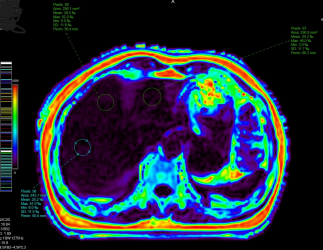

近日,玉溪市中山医院医学影像科在中山大学第一附属医院驻岗专家张朝晖教授指导下,利用联影uMR880 3.0T磁共振成功完成数例肝脏脂肪定量分析,帮助患者排除肝脏脂肪健康隐患。

磁共振检查主要为波谱检查和基于水脂分离技术获得质子密度脂肪分数(proton density fat fraction,PDFF)图是磁共振评定肝脏脂肪的两种方法。其中磁共振波谱检查技术要求较高,后处理较复杂;检查的扫描时间长,且一次扫描只获得肝脏的局部数据,很难全面了解肝脏情况。

基于水脂分离技术获取PDFF图的方法则比较实用,属于无创性检查,也是目前医学影像科正在开展的评定肝脏脂肪的方法。此技术能全面检查肝脏,扫描时间短,后处理方便。稳定性、准确度、精密度高,被认为是评估肝脏脂肪含量的客观有效方法,可为脂肪肝的早期诊断、分级、治疗策略选择和预后评估提供重要的信息。

在PDFF图勾画多个感兴趣区测量相应PDFF值以评估脂肪肝程度